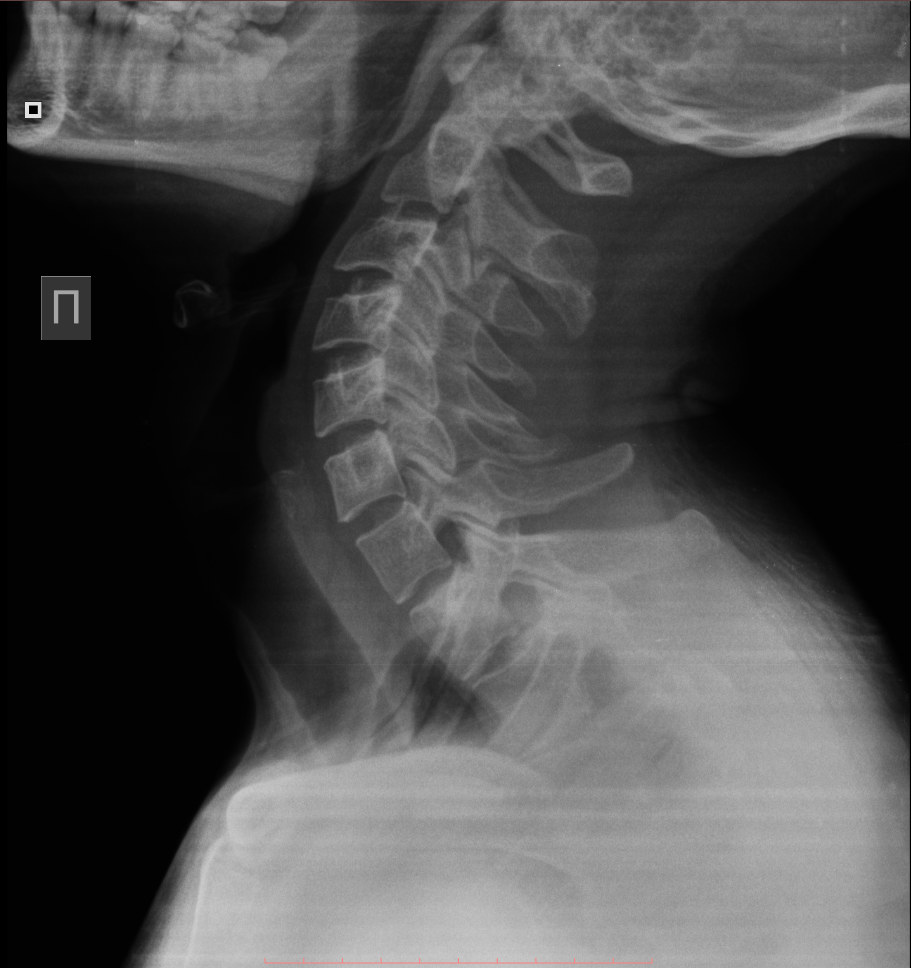

Медицинские снимки: рентген позвоночника сбоку